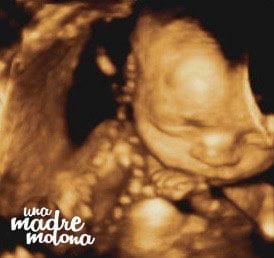

Y sin más dilación, os presento a ¡¡¡Minimolona!!!

¿No os parece increíble lo bien que se ve? marido y yo (bueno, y el resto de la familia molona) babeamos sin parar 😀 La chiquitina se pasó media sesión jugando con el cordón umbilical, lo cogía, se lo metía en la boca, lo volvía a soltar… ¡se mueve muchísimo!